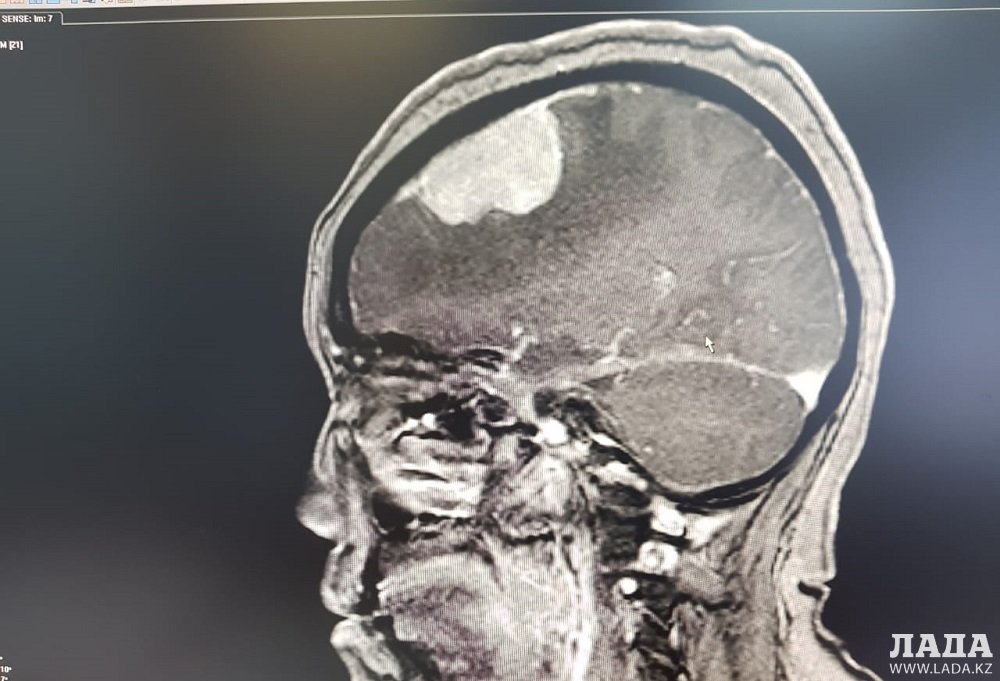

Медицина и хирургия: что нужно знать о трепанации